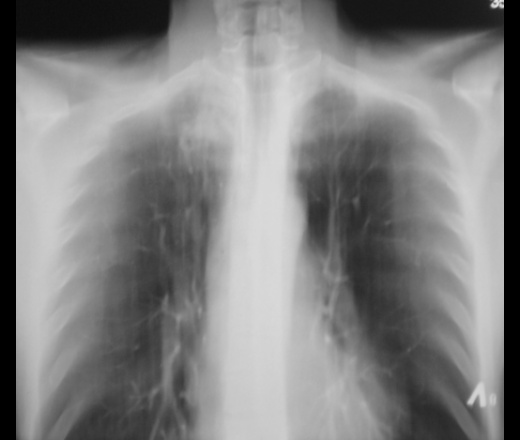

Инфильтрат с распадом?

Да, вроде "дырочка" видна... А, жалоб нет, пациент возмущен и буйствует.

А с левой верхушкой и апикальной плеврой все в порядке? Или придумала уже, что-то мне там тоже множественные мелкие тени кажутся.

На мой взгля, слева субплеврально довольно наглые очаги дозревают.

Ну, тогда где наши профи-тубы, дело к Nikolas? Дело в том, что справа этот инфильтрат довольно интенсивный, даже плотненький, хотя и с распадом вроде. Как бы не проснулись старые архивные дела с их отсевом.